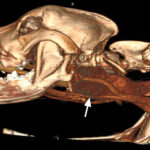

Approximately one month later, the dog was returned by the owners to CUVS for computerized tomographic analysis. The analysis revealed a large mass located in the deep tissues of the upper cervical region, which was suspected to be associated with the carotid artery or body or both (Figure 3a-b). The appearance of the thyroid glands was unremarkable. Small brain lesions (Figure 3a) and pulmonary nodules were also noted. Splenic nodules were still present (Figure 3c).